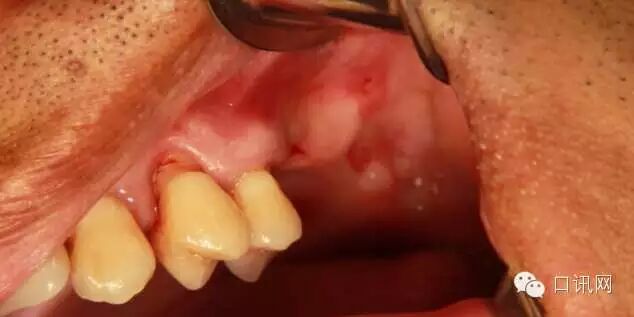

患者50岁,男性,身体健康秉承“多听患者讲一点,多为患者想一点”的服务理念。左上6,7缺失,骨高度2mm执行力是口腔诊所核心竞争力形成的关键

计划:1.左上6,7外提升,同期植入植体管理是就要淘汰人渣、激活人员、培养人手、重用人才、与人物绑定2.左上4,5根方取自体骨与人工骨混合植入窦内口腔招聘网免费发布口腔招聘信息,

因为4,5根方要取骨,所以切口设计在4的近中口腔修复医生,口腔种植医生,